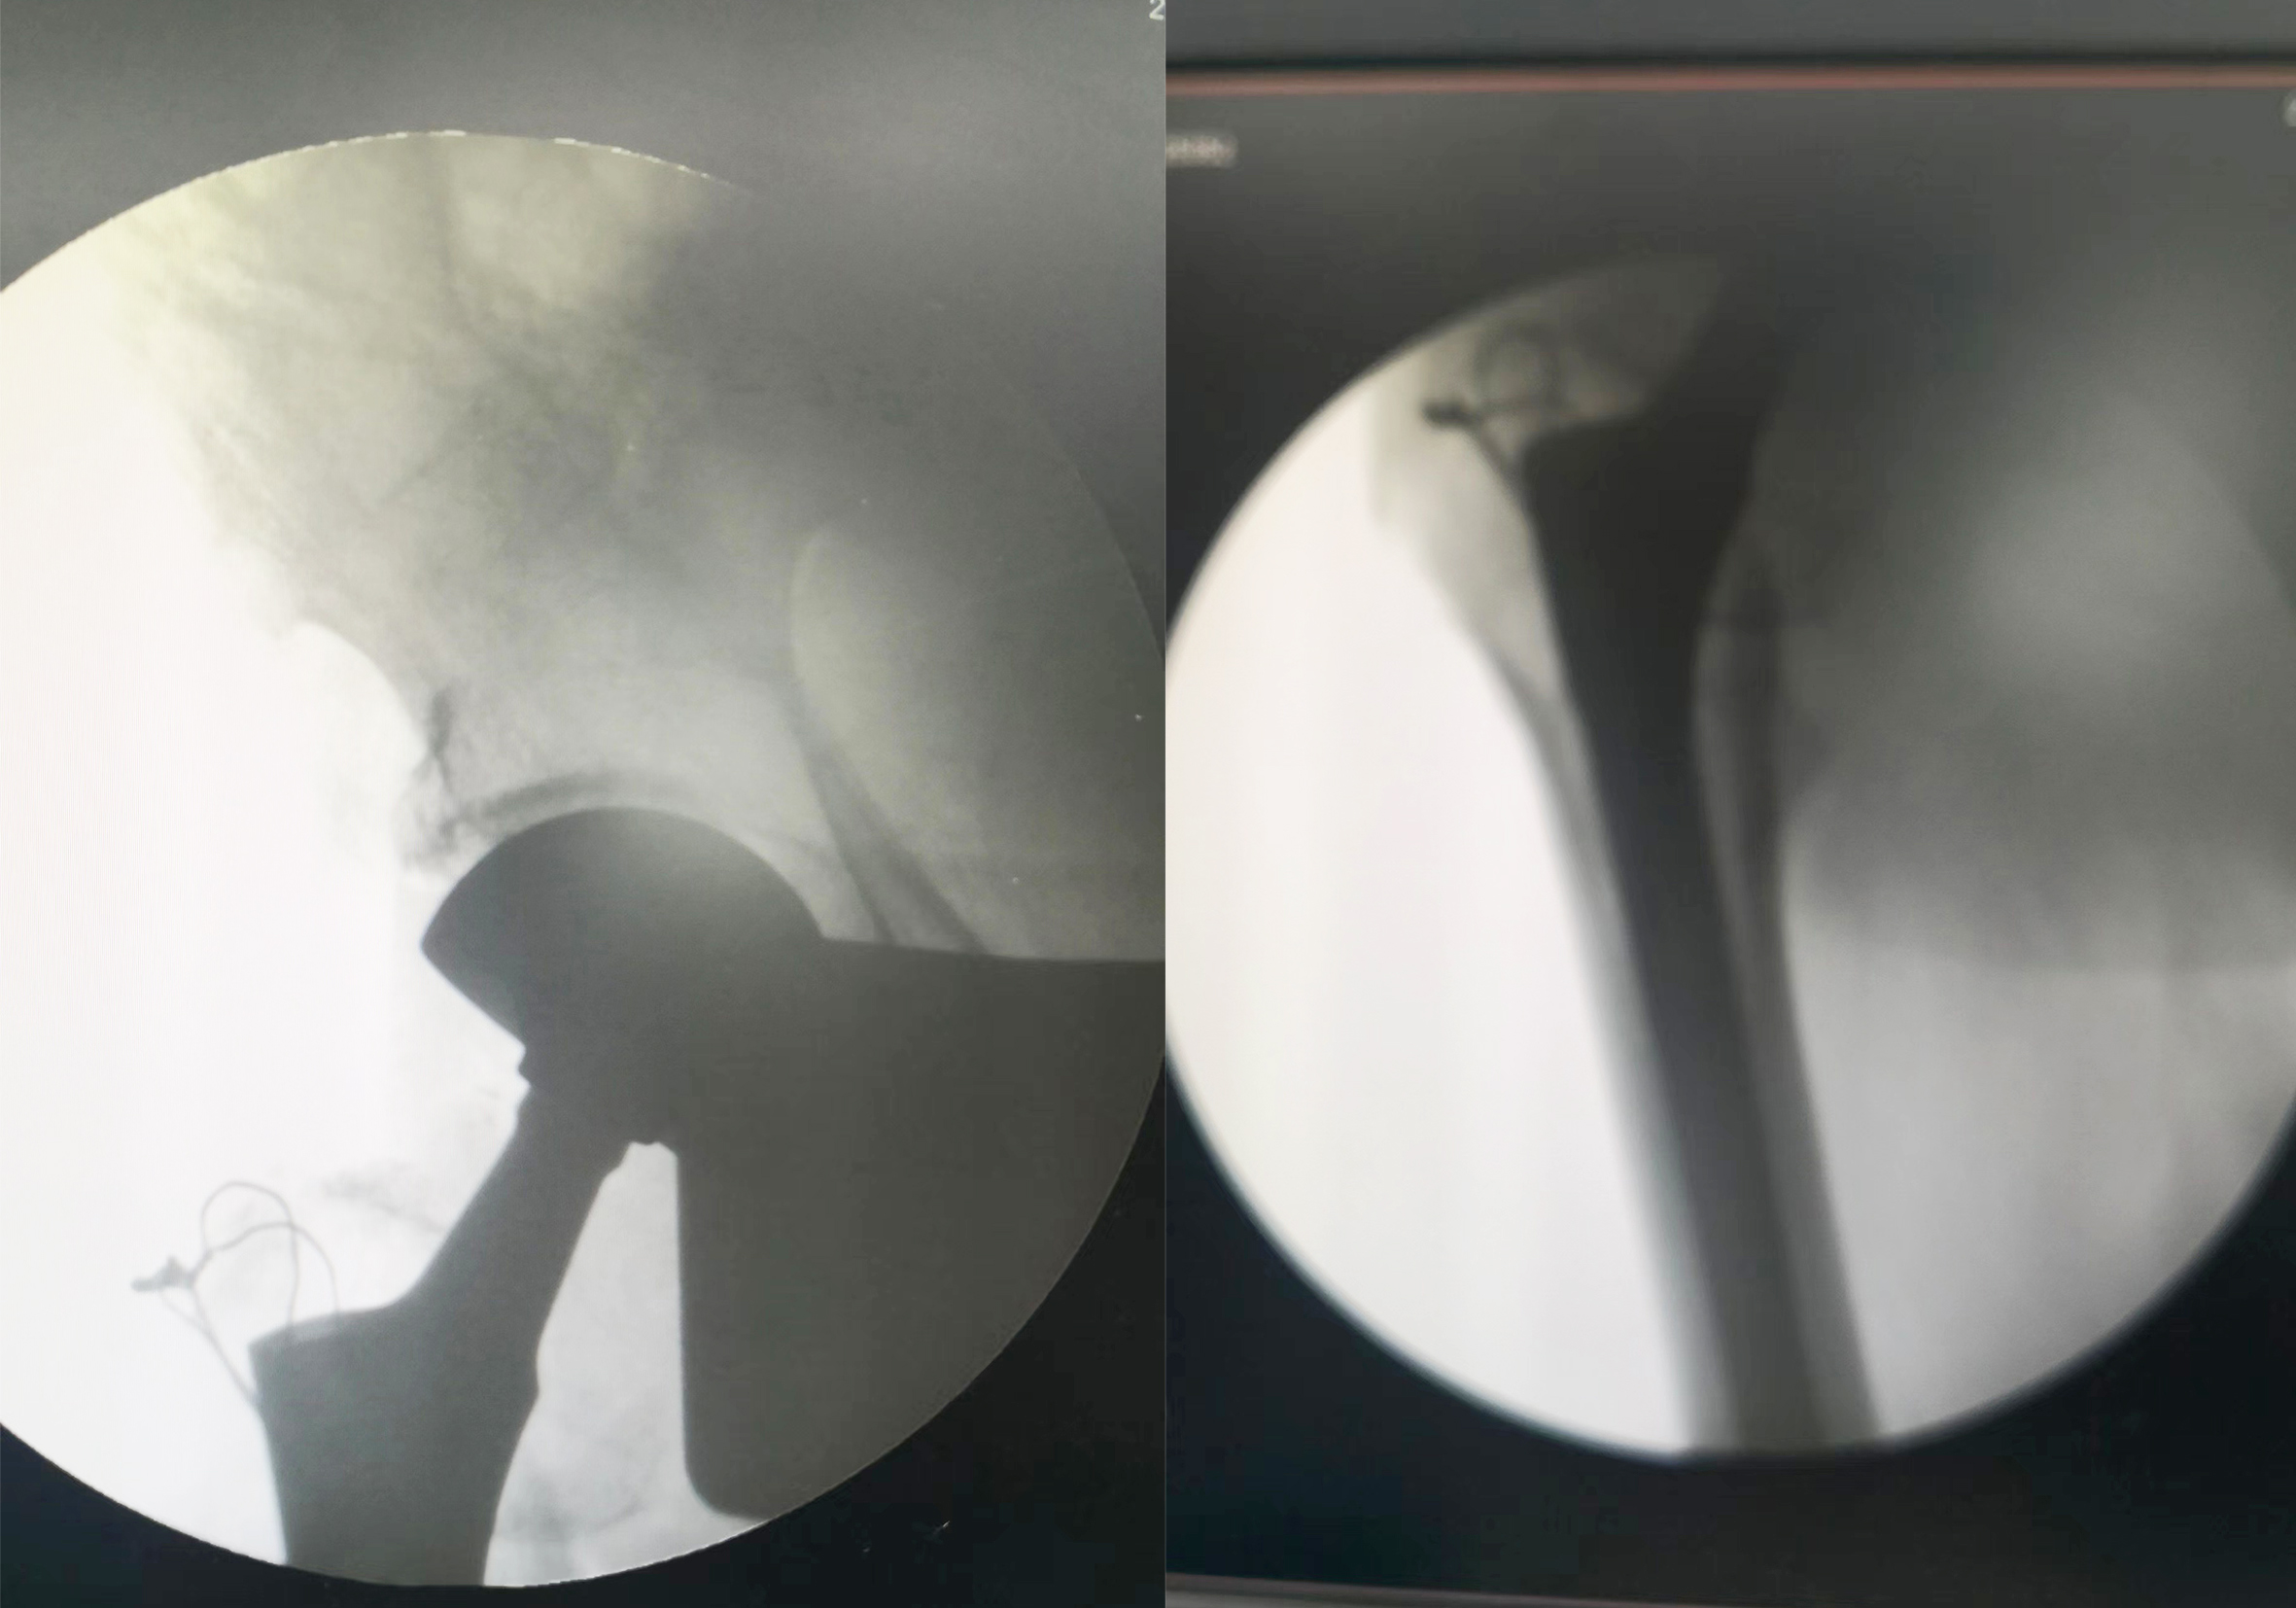

找庞润明主任治疗。诊断为:左股骨粗隆间骨折。 图说:患者术前DR片 入院后给予详细查体,经心电图室、CT室、化验室等各科室的共同配合下,迅速完善各项术前检查。通过庞润明主任及主管医生认真评估,分析了可能遇到的各种困难,决定老人可以行手术治疗。 图说:患者术中DR片 在手术室人员的共同配合下,手术顺利完成,术后髋关节正侧位DR 片,手术非常成功。 图说:患者术后DR片 股骨头置换术后的护理同样非常的重要,护士对大爷及家属进行了健康宣教,帮助患者做了如何坐立、上下床的练习,最终在我们医护人员的共同努力下,患者下地走路了,露出了满意的笑容。 图说:在医护人员的指导下患者下地走路 通过我们全体医护人员的精心照顾,细心的呵护,点点滴滴的付出,给患者鼓足了勇气,更加有信心面对病痛的折磨,战胜了病魔的纠缠。健康所系,性命相托!我们骨科全体医护人员竭诚为您服务!